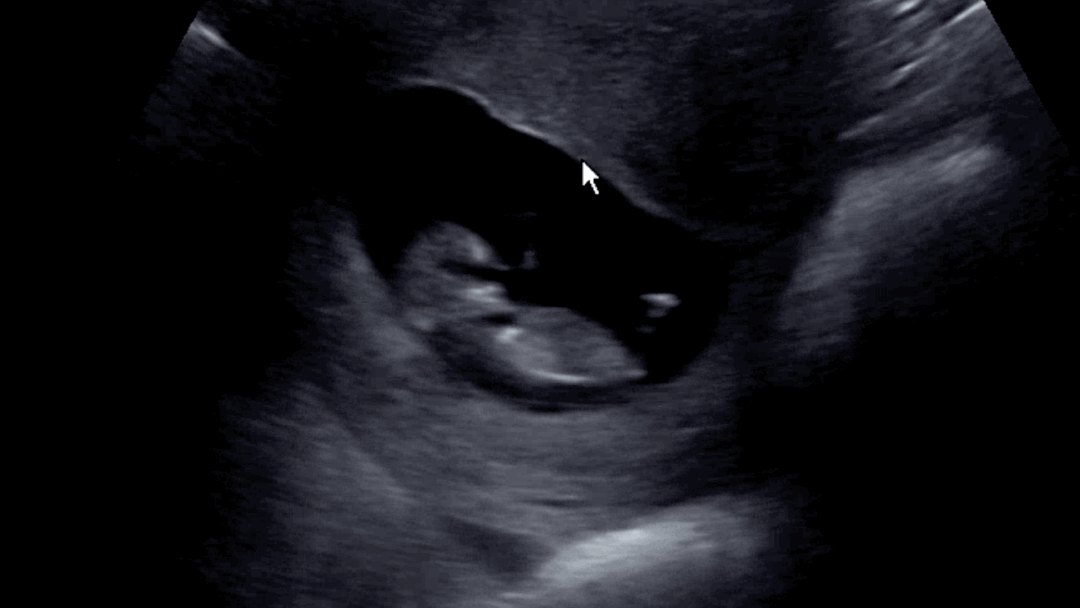

저도 초음파 올려봅니다(펄쩍 뛰는 아기)

저는 시험관 임신이고 오늘 드디어 난임병원 졸업을 하고 분만병원에서 첫 진료를 봤어요! 초음파 보기 시작하자마자 아가가 갑자기 펄쩍 뛰더니 초음파 보는 내내 계속 움직여서 웃참 실패하고 선생님도 빵터지셔서 웃다가 끝난 첫 진료였네요😂

마자요 처음으로 배초음파로 아가 봤는데 너무너무 신기하고 귀엽고 웃겼어요🥹 다음 초음파에도 빵터지면 곤란하니까 웃음참기용 슬픈생각 몇개 준비해가야겠어요!!!ㅎㅎ

너무 펄쩍 뛰길래 순간 잘못봤나 했어욬ㅋㅋㅋ옆모습 보여주다가 갑자기 뒤돌아버리고ㅠㅠ하 너무 귀여워서 영상 백번 돌려본 것 같아요🥹